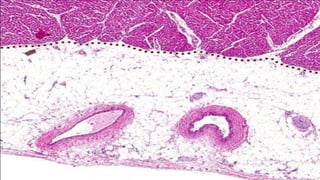

Esquema de Capilar Sinusoide con membrana basal

incompleta

Imagen histológica de capilar sinusoide de hígado

• Tienen un diámetro luminal mayor al de los capilares normales

• Las paredes con amplias hendiduras entre las células endoteliales

• Lamina basal incompleta

• Presentes en hígado y órganos hematopoyéticos como la medula ósea y el